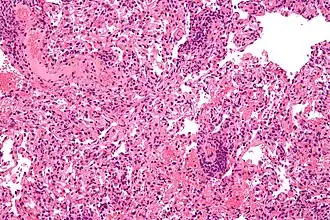

Реа́кция отторже́ния транспланта́та — иммунный ответ реципиента на пересадку чужеродного органа или ткани (аллотрансплантацию). Относится к реакциям трансплантационного иммунитета. Различают молниеносное (развивается через минуты после подключения органа к кровотоку), острое (0-3 недели после операции) и хроническое отторжение (через несколько месяцев или позже).